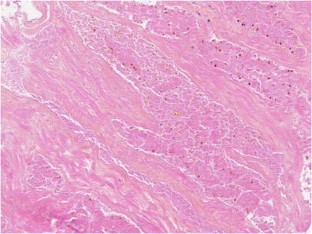

Low-risk prostate adenocarcinoma is classically managed either with active surveillance or radical therapy (such as external radiotherapy or radical prostatectomy), but both have significant side effects. Vascular-targeted photodynamic therapy (VTP) is a focal therapy proposed as an alternative approach for localized, low-volume, and low-Gleason score (≤6) carcinomas. We report histological modifications observed in prostate biopsies of 56 patients, performed 6 months after VTP using the photosensitizer TOOKAD® Soluble (WST11) and low-energy laser administered in the tumor area transperineally by optic fibers. In 53 patients, we observed sharply demarcated hyaline fibrotic scars, with or without rare atrophic glands, sometimes reduced to corpora amylacea surrounded by giant multinuclear macrophages. Mild chronic inflammation, hemosiderin, and coagulative necrosis were also observed. When residual cancer was present in a treated lobe (17 patients), it was always located outside the scar, most often close to the prostate capsule, and it showed no therapy-related modification. Histopathological interpretation of post-WST11 VTP prostate biopsies was straightforward, in contrast with that of prostate biopsies after radio or hormonal therapy, which introduces lesions difficult to interpret. VTP resulted in complete ablation of cancer in the targeted area.